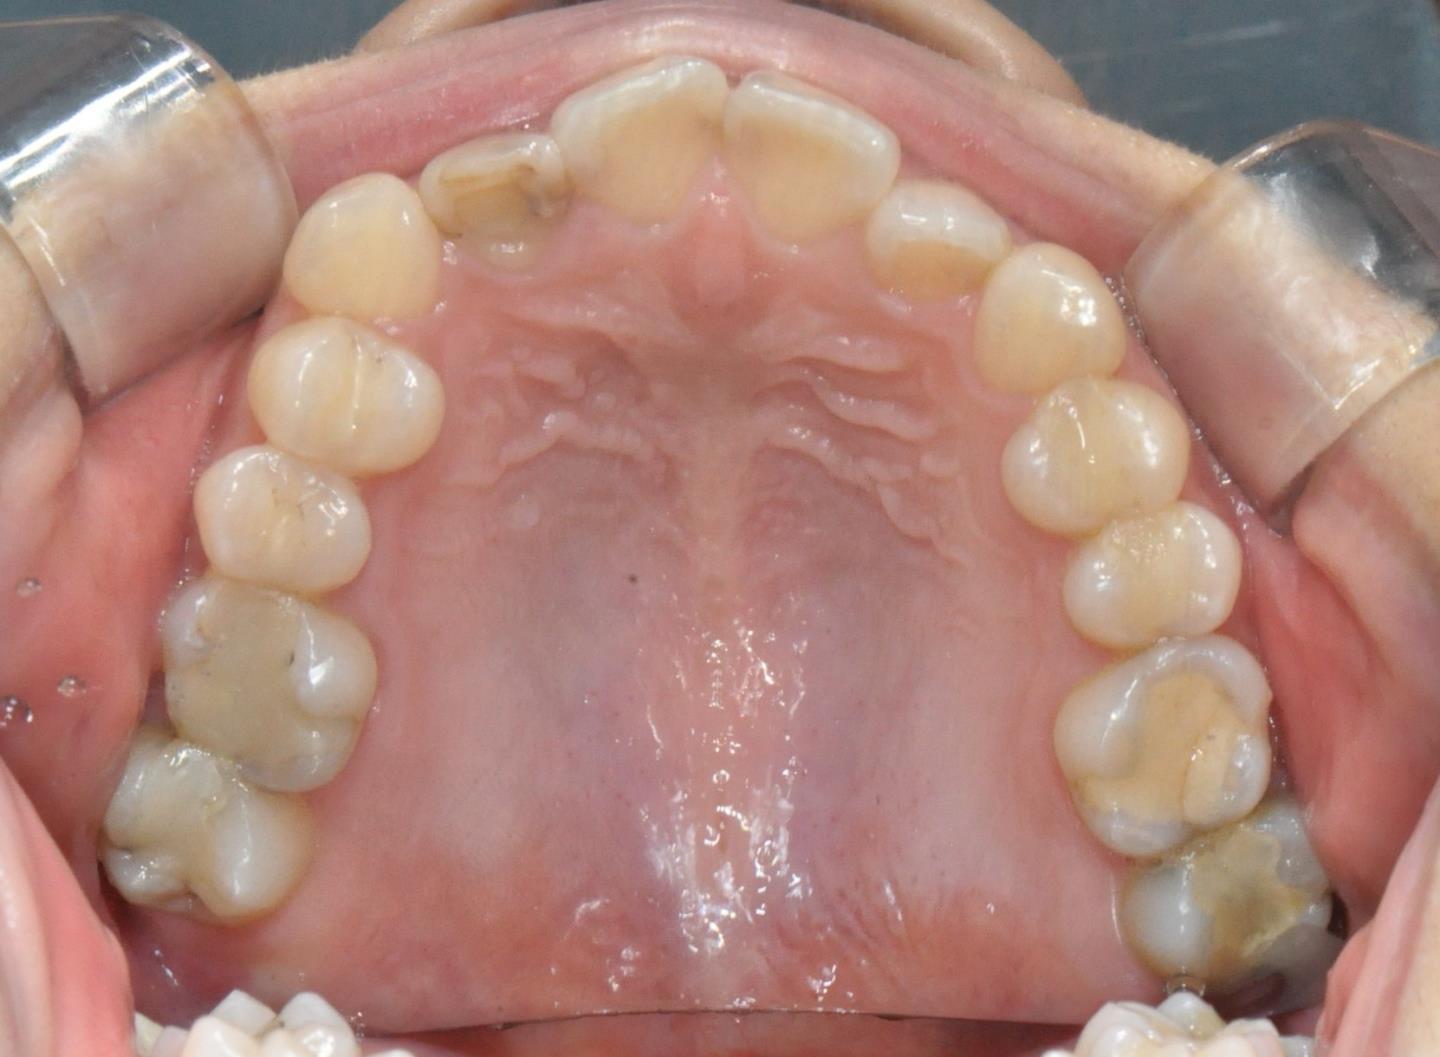

그때 가서 찍은 사진이고,

치료 받기 전 찍은 사진입니다.